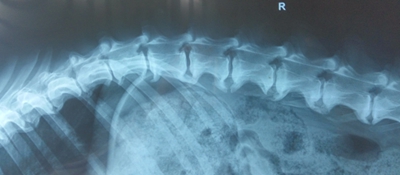

该犬双后肢不能站立,触诊胸腰结合部时有疼痛反应,双后肢无本体反射,有深痛。膝跳反射减弱。影像学检查显示胸腰椎广泛性起止点病,T12-T13,L1-L4椎间孔密度升高,椎间盘钙化(图2)。外科初诊为L1-L2椎间盘突出,脊髓损伤。采用激素冲击疗法,治疗过程中犬出现胃肠道出血,停用激素,进行对症治疗,输液支持疗法。治疗后犬后肢状况没有明显好转,仍然无法站立行走。可以自主排大小便,排尿时偶尔可以站立,主要以前肢负重,双后肢拖行,脚背着地。犬呕吐较频繁,呕吐物中有红色液体,排黑色稀便,食欲不振,精神状况差。3月26日转中医进行针灸和中药治疗。

图2:腰椎段右侧位影像学